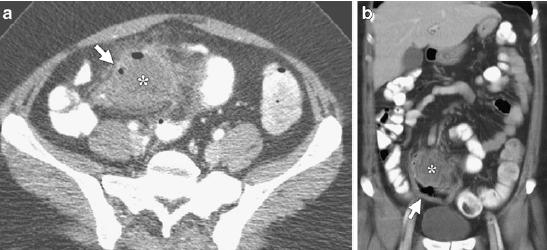

Hình 26: Túi thừa Meckel lộn ngược ở bệnh nhân nam 31 tuổi. A, CT uống và tiêm cản quang, thấy khối lồng hồi manh tràng, có “target sign” (đầu mũi tên). B, Vùng trung tâm là lõi dài đậm độ mỡ (mũi tên. Sau mổ là túi thừa Meckel lộn ngược . (Angela D. Levy, Christine M. Hobbs (2004). Meckel Diverticulum: Radiologic Features with Pathologic Correlation. RadioGraphics 24:583).